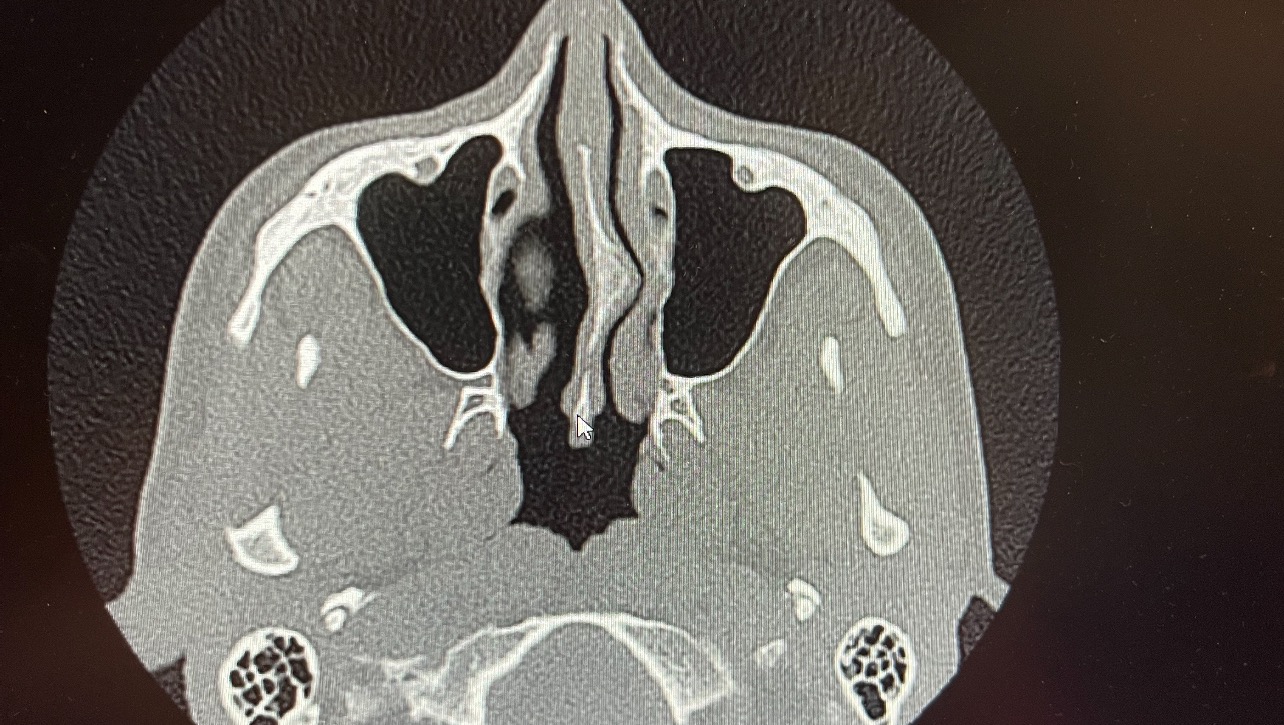

Hello fans and friends I am reaching out for help from everyone who can help me stay alive. I need an emergency surgery due to a on going MRSA infection from 2016. My insurance is not covering the cost due to it being a preexisting condition. I need this surgery so it does not continue to spread and develop into sepsis. My infection has started to spread though my face and neck which is causing extreme swelling and making it very hard to breathe. I’ve been on all the anabiotic’s and nothing works. My only chance of beating this resistant infection is surgery and antibiotic IV infusion for 4 - 6 weeks following surgery. So as a last resort I am reaching out and asking all of you for your help! I sincerely appreciate your support.